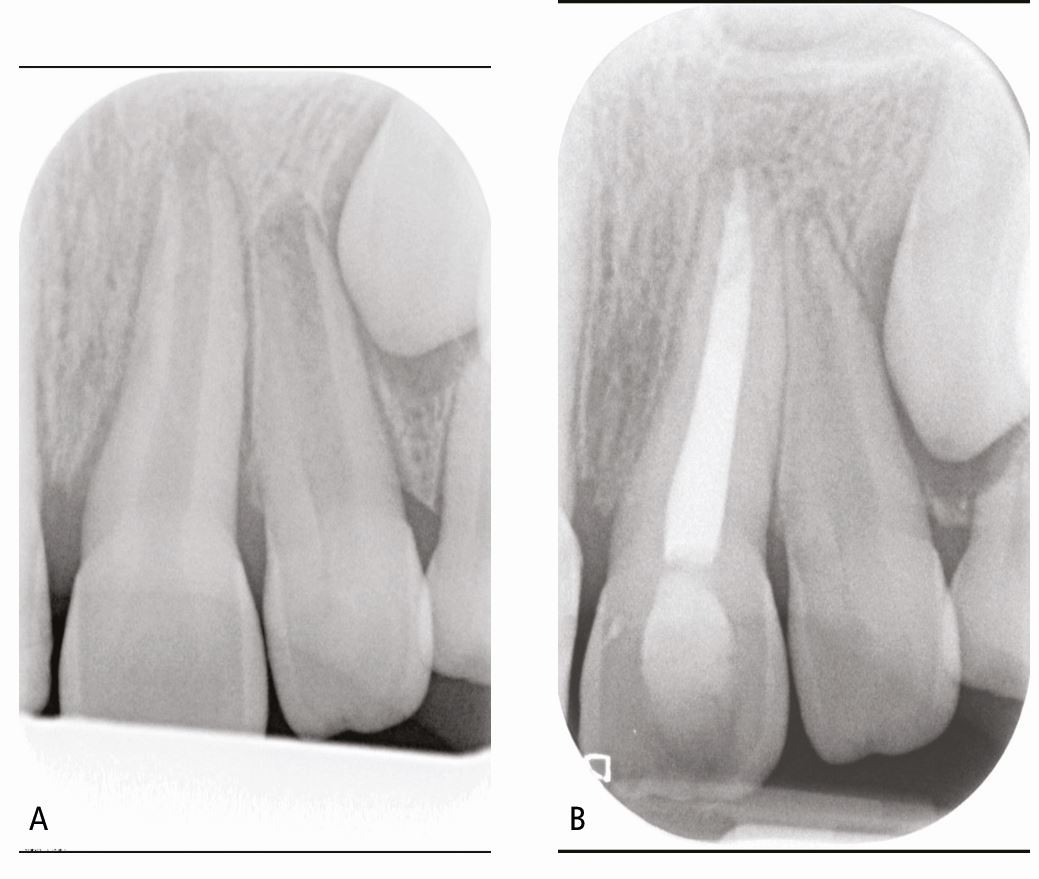

Fig. 8

From: Getting it right at every stage: Top tips for traumatic dental injury review: Part 2

A) Showing tooth 21, which became non-vital in an 8-year-old girl. This has an open apex and was managed by formation of an apical barrier using MTA. B) Shows completed root canal which was obturated using thermoplastic gutta percha